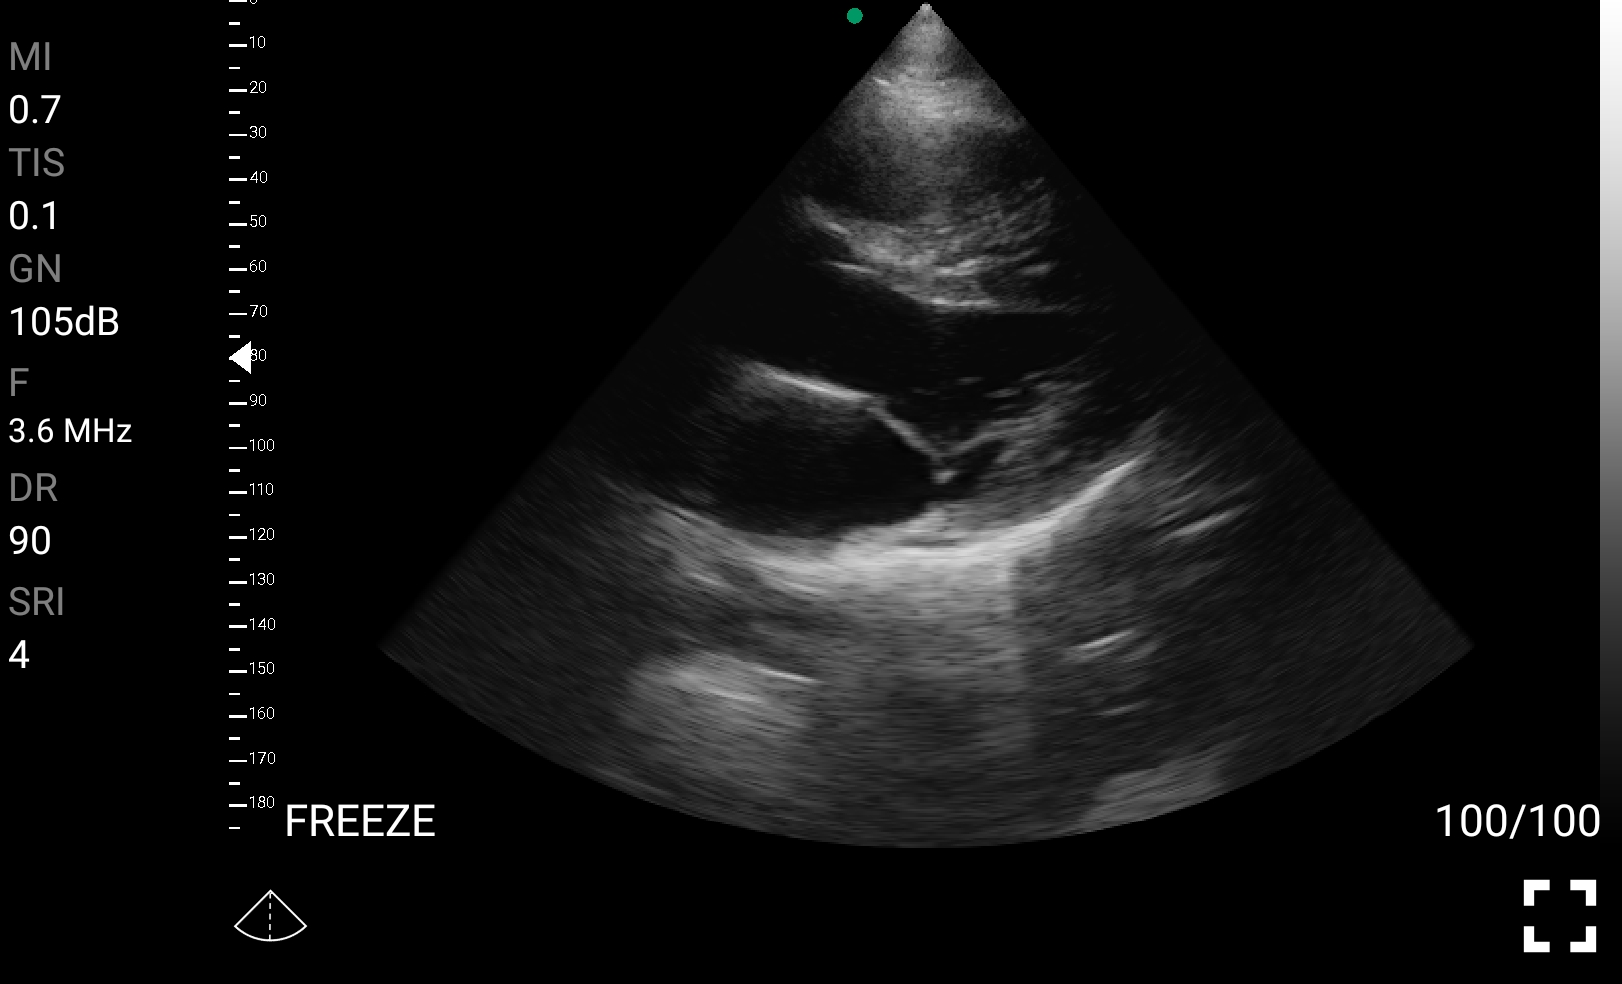

• Καρδιολογική Απεικόνιση για Κλινική Αξιολόγηση

• Εκτίμηση κλάσματος εξώθησης (EF): Προσέγγιση της συστολικής λειτουργίας της αριστερής κοιλίας.

• Διάγνωση περικαρδιακής συλλογής: Εκτίμηση πιθανής καρδιακής επιπωματισμού.

Παραδείγματα

Ολες οι παραπάνω απεικονιστικές εξετάσεις έχουν ληφθεί από φορητή συσκευή όπως: Apple Iphone, Tablet, Samsung Mobile Phones και διάφορες άλλες φορητές συσκευές.

Παραδείγματα Video